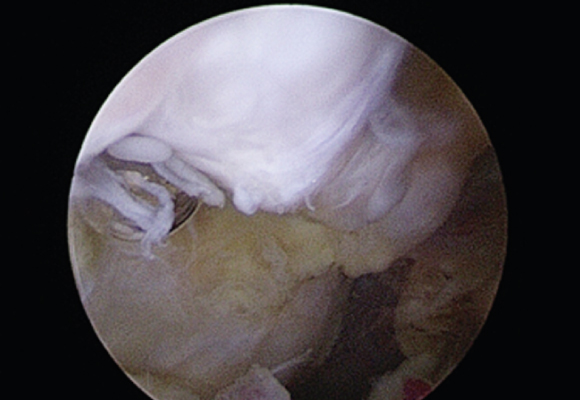

혈관이 있는 부위에 파열이 발생한 경우 연골판을 봉합해 주는 수술 시행

ㆍ환자 동의를 받은 자료이며, 이미지 사진은 실물과 다를 수 있습니다. (22.06.09)